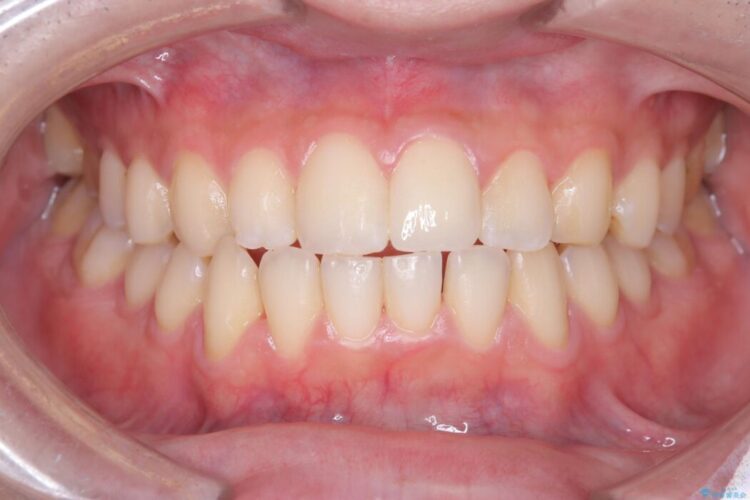

メタルフリー|全ての銀歯をセラミックへ

メタルフリー|全ての銀歯をセラミックへ ビフォー メタルフリー|全ての銀歯をセラミックへ アフター

口腔内の銀歯を全て無くし、白く健康的な状態にしたいとご来院された患者様です。